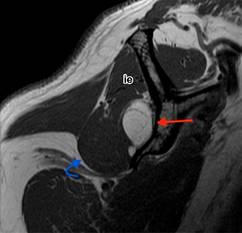

En el estudio de resonancia magnética entre fibras musculares del infraespinoso se observa imagen ovoidea, de márgenes bien delimitados, isointensa al tejido graso en secuencias T1, T2 y densidad protónica con saturación grasa, con diámetros aproximados en plano axial de 5.5 × 1.3 cm, en plano sagital de 3.1 × 1.4 cm y en coronal de 3.8 × 2.9 cm, con imágenes lineales internas hipointensas en todas las secuencias menores de 2 mm (Figura 1). La lesión se extiende por toda la fosa infraespinosa con involucro de algunas fibras musculares del redondo menor y desplaza levemente el infraespinoso (Figura 2).